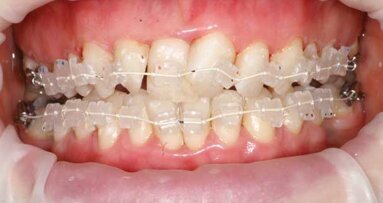

Fig. 2: Pre-op retracted view showing the diastema and improper proportions of the width-to-length ratios.

A 24-year-old female patient in excellent medical and good dental health presented stating she had not been to the dentist in some time and wished to improve her oral health and the appearance of her teeth. The pa­tient was unhappy with the shape and shade of her teeth. She was particularly concerned with the im­proper proportions of the width-to-length ratios of her incisors and the diastema present between teeth #11 and 21 (Figs. 1 & 2).4 Several areas of gingival asymmetry were also noted. The patient stated that she had re­ceived orthodontic treatment in the past, and cos­metic bonding (which had already failed at the time of her presentation) to close the diastema between teeth #11 and 21. She expressed her desire to have a beautiful, brighter and natural-looking smile.